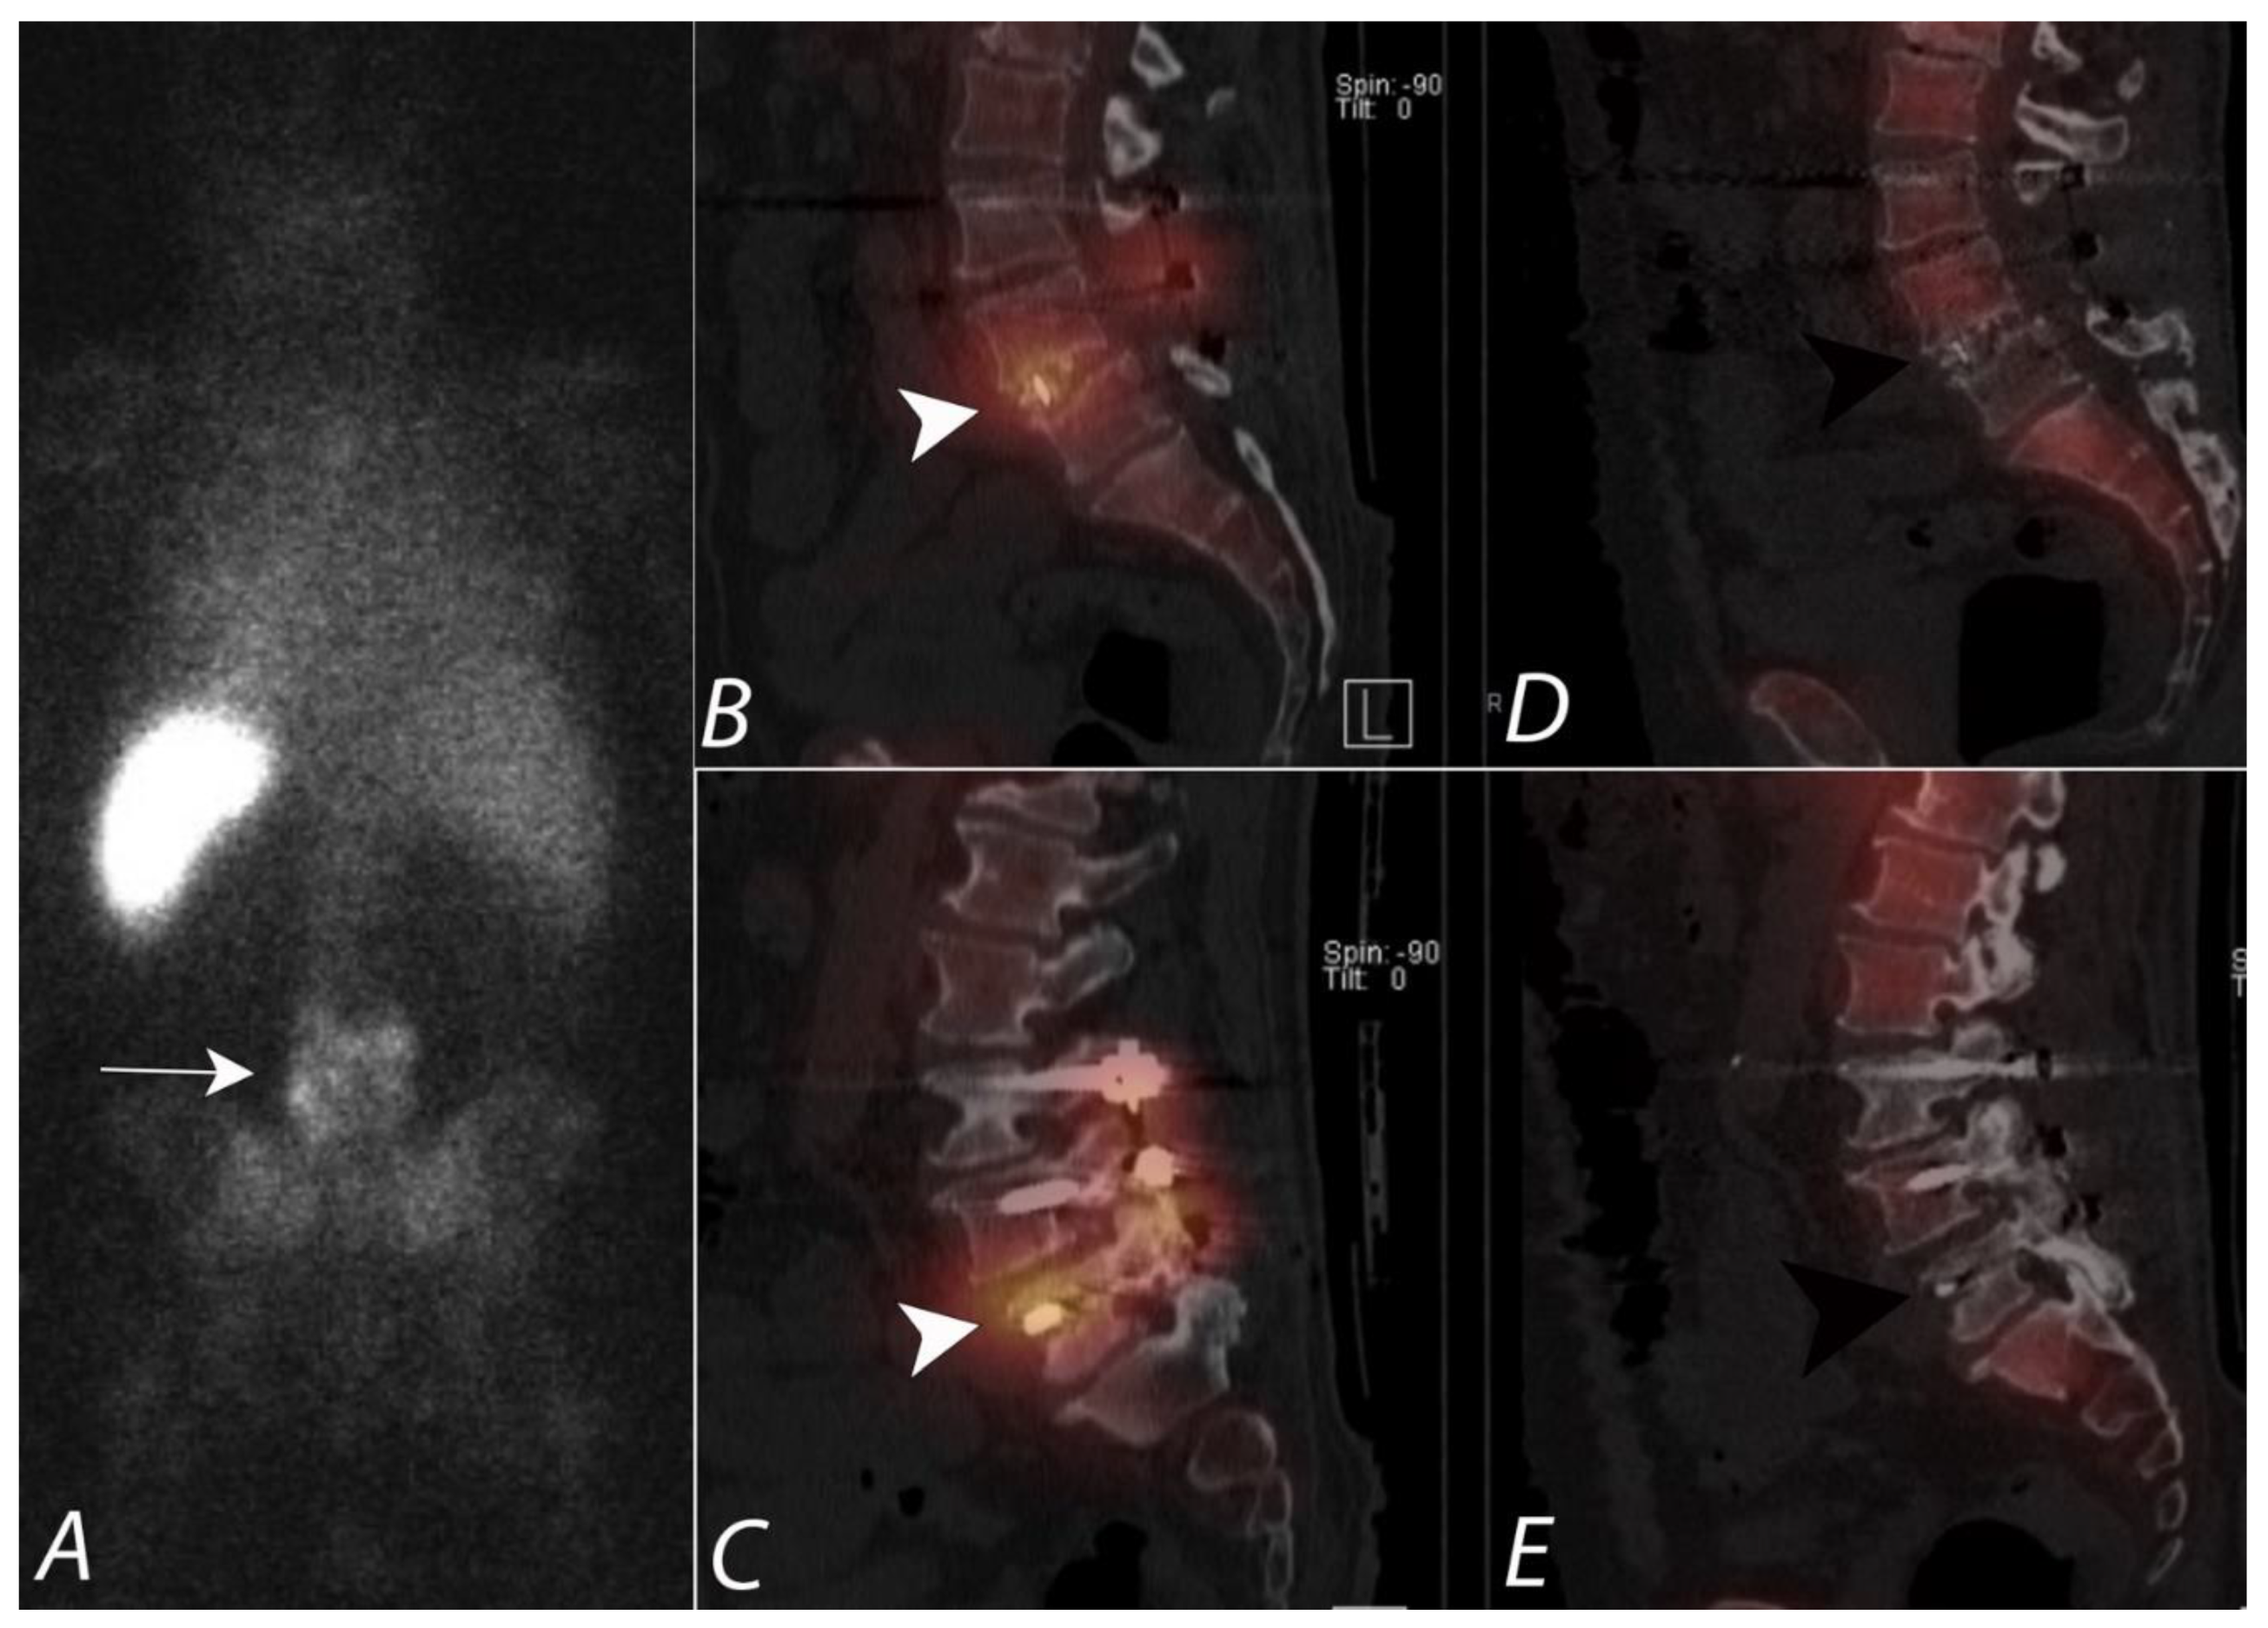

Figure 13.

Seventy-two-year-old male with draining posterior lower lumbar wound one month after dorsal decompression and bilateral dorsal fixation from L3 to S1. Posterior planar image from an 111In leukocyte (WBC) scan (A) demonstrates heterogeneous uptake of tracer activity localizing to the lower lumbar region (white arrow). Sagittal SPECT/CT images of the 111In WBC scan (B,C) show increased uptake of labeled WBCs in the soft tissues, posterior elements, disc space, and vertebral bodies at L4-5. (white arrowheads). However, sagittal SPECT/CT images from 99mTc sulfur colloid scan (D,E) demonstrate no focal uptake (black arrowheads) and is incongruent with the 111In WBC distribution of activity. This supports that a pyogenic infection is present involving the L4-5 vertebrae, posterior elements, and disc spaces. The absence of uptake on sulfur colloid confirms that the uptake of WBCs is not due to a granulation tissue due to mononuclear cell infiltration in chronic inflammation.